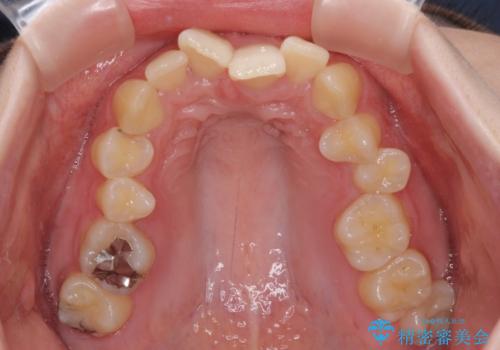

- 全体的な歯列の叢生を気にして来院された患者様です。

奥歯の咬み合わせを見ると、片方は上顎が下顎に対して相対的に前方にあり、他方は交叉した咬合の状態でした。

咬み合わせを改善するためには、上顎臼歯を後方に移動させた咬み合わせにする必要があります。

インビザライン単体で改善することも可能ですが、ディープバイトのためインビザライン単体で達成する可能性が低いと考えられたため、カリエール・ディスタライザーという補助装置を併用して、より確実性を上げることとしました。

カリエール・ディスタライザーを使用している期間、反対側はワイヤー矯正により叢生を解消していくこととしました。

奥歯の咬み合わせを改善しながら、並行してインビザラインで歯列を整えることとしました。